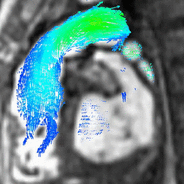

Blood flow can be visualized and quantified on scans acquired with a scan sequence called 4D flow. These volumetric scans capture multidirectional flow values anywhere within the imaged volume throughout the cardiac cycle, leading to a comprehensive exam of the entire anatomy.[15] Visualization can display flow velocity maps, vectors and streamline

4D flow visualization. flow (left) and streamlines (center) and vectors (right).